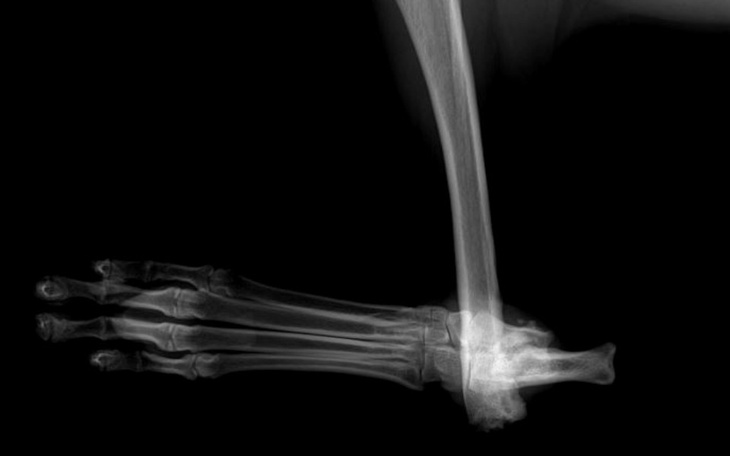

Bucki został zabrany do ortopedy i chirurga aby dowiedzieć się co możemy zrobić z łapą. Zostało wykonane zdjęcia RTG oraz badania z zakresu ruchu i bolesności.

OPIS BADANIA: Pies ma uraz prawej kończyny miedniczej - widoczne złamanie stawu skokowego, chodzi na kości piszczelowej - na kikucie. Wiemy, że łapa sprawia Buckiemu ogromny ból przy poruszaniu się i każdym dotyku, wiemy również, że możemy ją zoperować i uwolnić tym sam Buckie od bólu, a przede wszystkim dać mu szanse nowe życie! Bucki musi przejść operacje artrodezy stawu skokowego na płycie. Koszt takiej operacji szacowny jest na 4500 zł to ogromna kwota, ale wiemy, że z Wami uda nam się ją uzbierać i Bucki otrzyma nowe życie! Życie bez bólu oraz większe szanse na prawdziwy dom!